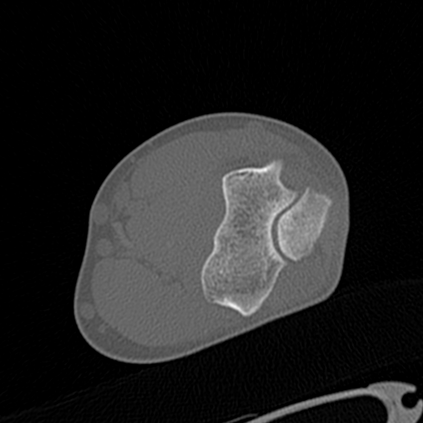

CT reconstruction provides radiologists with images for diagnosis and treatment, yet current deep learning methods are typically limited to specific anatomies and datasets, hindering generalization ability to unseen anatomies and lesions. To address this, we introduce the Multi-Organ medical image REconstruction (MORE) dataset, comprising CT scans across 9 diverse anatomies with 15 lesion types. This dataset serves two key purposes: (1) enabling robust training of deep learning models on extensive, heterogeneous data, and (2) facilitating rigorous evaluation of model generalization for CT reconstruction. We further establish a strong baseline solution that outperforms prior approaches under these challenging conditions. Our results demonstrate that: (1) a comprehensive dataset helps improve the generalization capability of models, and (2) optimization-based methods offer enhanced robustness for unseen anatomies. The MORE dataset is freely accessible under CC-BY-NC 4.0 at our project page https://more-med.github.io/